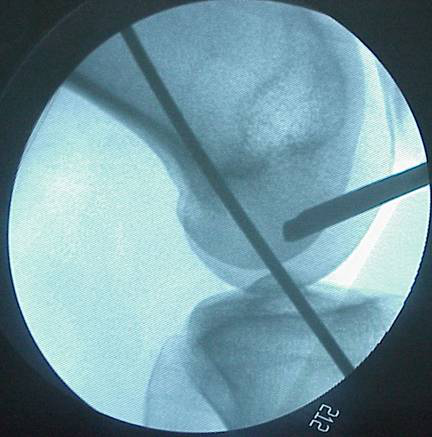

脛骨點(diǎn)選取